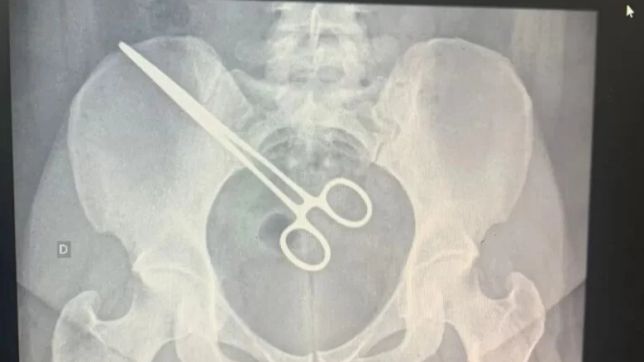

A Santa Casa de Araçatuba, no interior de São Paulo, apura a conduta de médicos que esqueceram uma pinça dentro do corpo de uma paciente após uma cirurgia. Ela teria descoberto o objeto, muito parecido com uma tesoura, ao visitar o marido em um presídio e passar por um detector de metais.

O caso foi revelado pela TV TEM e confirmado pelo Metrópoles. À emissora, a sogra da paciente afirmou que a pinça foi encontrada pelo detector de metais no Centro de Detenção Provisória (CDP) de São José do Rio Preto, no interior paulista.

Em seguida, a mulher foi até a Santa Casa e confirmou que a pinça estava em sua região pélvica. No mesmo hospital, ela havia feito uma cirurgia em setembro.

A paciente foi novamente internada e o objeto foi retirado do seu corpo.